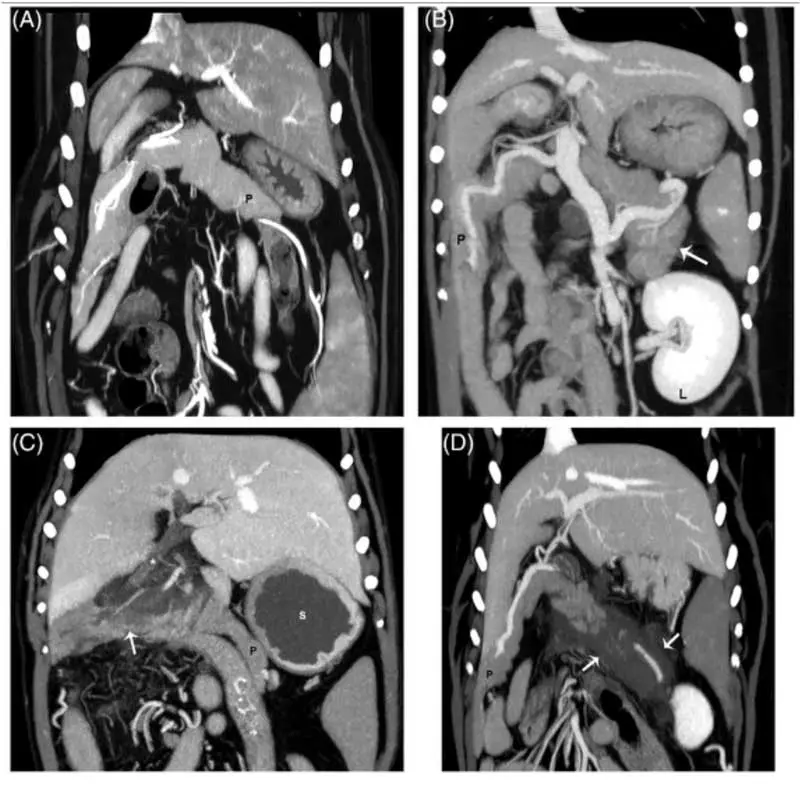

CT

With the increasing availability of CT, more dogs are likely being diagnosed in this way (Figure 4). Although AUS has traditionally been the main method, and indeed changes are often part of the inclusion criteria for studies, CT is considered the gold standard in diagnosing human pancreatitis50. An advantage of CT is that the entirety of the pancreas can be reliably visualised, which is possible in only three-quarters of dogs via ultrasonography, even by specialists18.

Heterogenous pancreatic contrast enhancement in people is a signifier of necrosis, a significant prognostic marker (some older evidence suggests this in dogs, too), and CT has been shown as a very sensitive test for this in dogs18. CT is superior to ultrasonography for identifying portal vein thrombosis (present in 10 out of 25 cases; Figure 2), which does have important prognostic importance18,20,21. However, despite all these advantages, CT has not yet been found to be superior to specialist ultrasonography for the actual diagnosis of CAP (for example, pancreatomegaly or mesenteric changes)18.